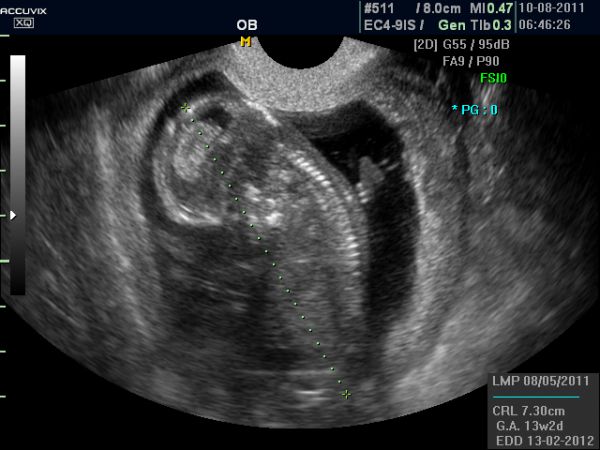

tak jsme dneska absolvovali NT screening...... byla jsem z toho docela vystrašená, ale nakonec vše dobře dopadlo. Celkové riziko nám vyšlo 1 / 13 100 takže radost veliká...

+ ještě přikládám utz ze 10tt